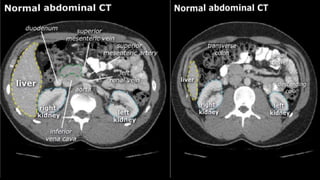

• A few characteristics of normal anatomy:

• Portal venous phase: the parenchyma of the

liver/spleen/pancreas is homogeneously enhanced.

• Intra-abdominal fat has the density of fat (HU -50 to -100;

see the X-ray/CT technique course for more information

about Hounsfield units); similar to normal subcutaneous fat.

If not, there may be ascites or fatty infiltration.

• A fewcharacteristics of normal anatomy: • Portal venous phase: the parenchyma of the liver/spleen/pancreas is homogeneously enhanced. • Intra-abdominal fat has the density of fat (HU -50 to -100; see the X-ray/CT technique course for more information about Hounsfield units); similar to normal subcutaneous fat. If not, there may be ascites or fatty infiltration.